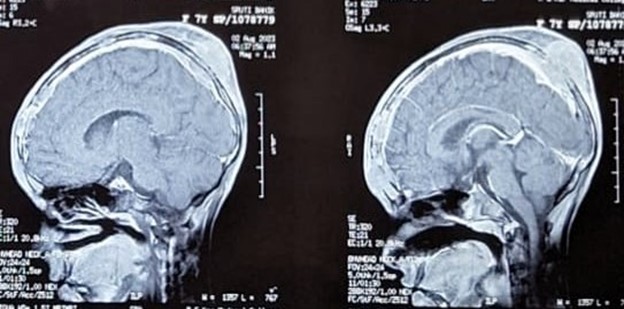

Figure 3: MRI brain (sagittal view) showing calverial metastasis

On Post operative evaluation, CECT THORAX on 21/5/23 did not reveal any obvious lesion. CECT Brain on 9/5/23, showed an Extra calvarial nonenhancing mild soft tissue swelling in right occipital (16X8mm) and mild bony erosion adjacent to soft tissue swelling. CECT whole Abdomen on 21/5/23 showed a Left paraaortic nodal mass(30x22mm) with Multiple vertebral and pelvic bony metastatic lesions, mild right hydronephrosis and bowel distension Considering a metastatic disease, she was then planned for multiagent chemotherapy. Unfortunately, the patient was lost to follow up for around 2 months.